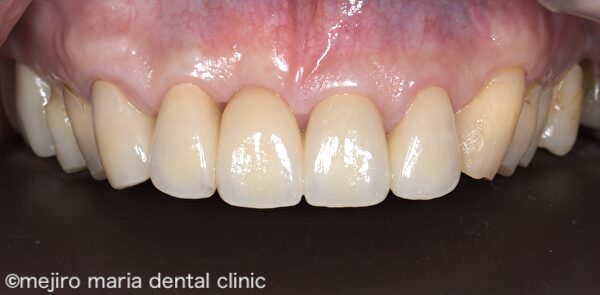

上記After 画像を見ると、歯肉形態が概ね生理的な状態に改善している事がわかります。この状態で歯肉の形態を整えながら治癒を待ち、約6ヶ月後に適合の良いブリッジを作製し装着しました。

治療後の様子

結合組織移植術(CTG)を行った後の歯肉は、安定するまでに半年近くかかると言われています。移植した歯肉は多少小さくなって、最終的なボリュームへと落ち着きます。治癒を待つのと並行して、歯肉の形をブリッジのポンティックが収まるような形態に整え、最終補綴物を作製、装着しました。歯肉の形態が生理的な状態へと改善されたことで、清掃性も上がり、審美性も高めることができました。